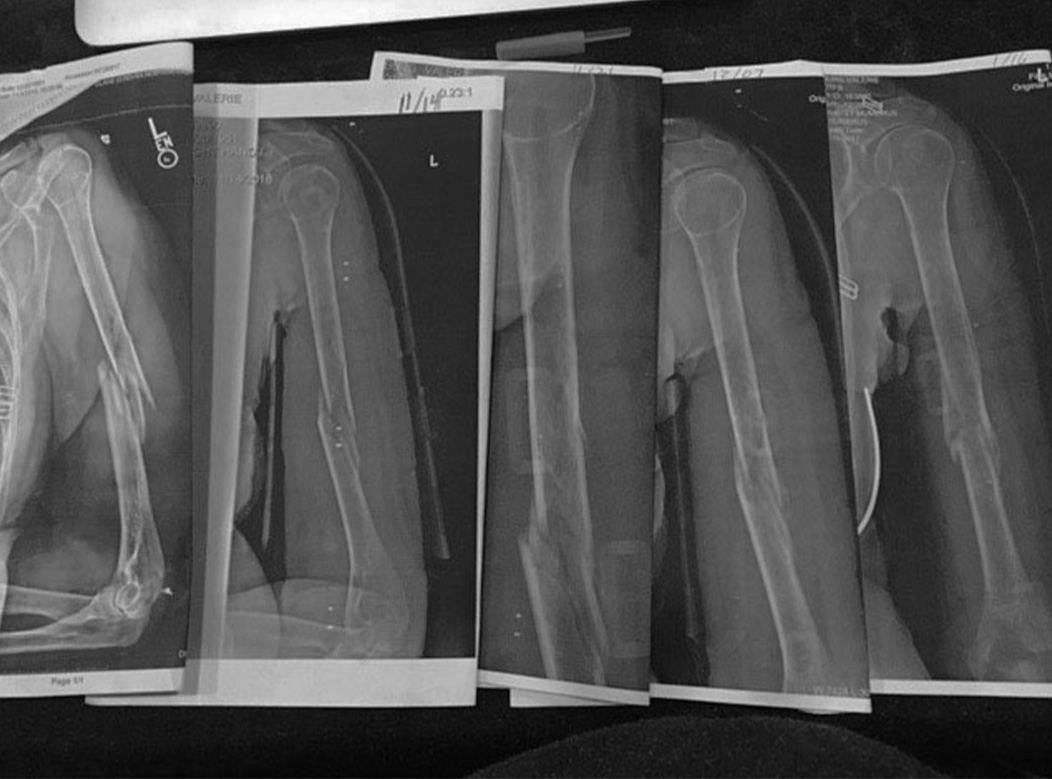

As you can see, I got to experience hand and arm healing from the inside. The series of x-rays that tracked my healing progress is shown in Figure 2. This process changed my life and got me thinking deeply about how we heal and the possibilities inherent in all our systems. My bone trauma physician said that it was not very glamorous to treat a broken arm with nothing, but he made it clear to me that he felt it best to rest the arm in gravity. He said “The best recovery is when I can assist in natural healing and take advantage of how the body and bone heals.” It was easy to agree to that logic. Let gravity be my therapist.

The time that took was quite a journey. The first x-ray on the left of Figure 2 is the day of the accident, the next one is ten days later, and the middle x-ray is seventeen days after accident. The second from the right is a month after the accident, and the image on the far right is two months post crushing. The bone had gone home in ten days in spite of enormous edema, pain, and bone distortion. Gravity brought it back into alignment and ‘home’. It was somewhere in those ten days that I had tried to move and couldn’t find my hand in space. The fibrous formation was clearly still being created.

Reading this quote got my full attention. My shoulder had no connectivity below the mid-humeral break. The proximal and distal pieces of my humerus, as you can see in the first x-ray of Figure 2, had no connection. The fascial elements were inflamed as well as the radial nerve. The movement of my shoulder to bring my hand to my face couldn’t find the path. I did not have a brain injury. So, what happens to our hand movements when our shoulders are restricted, inflamed, and immobilized?